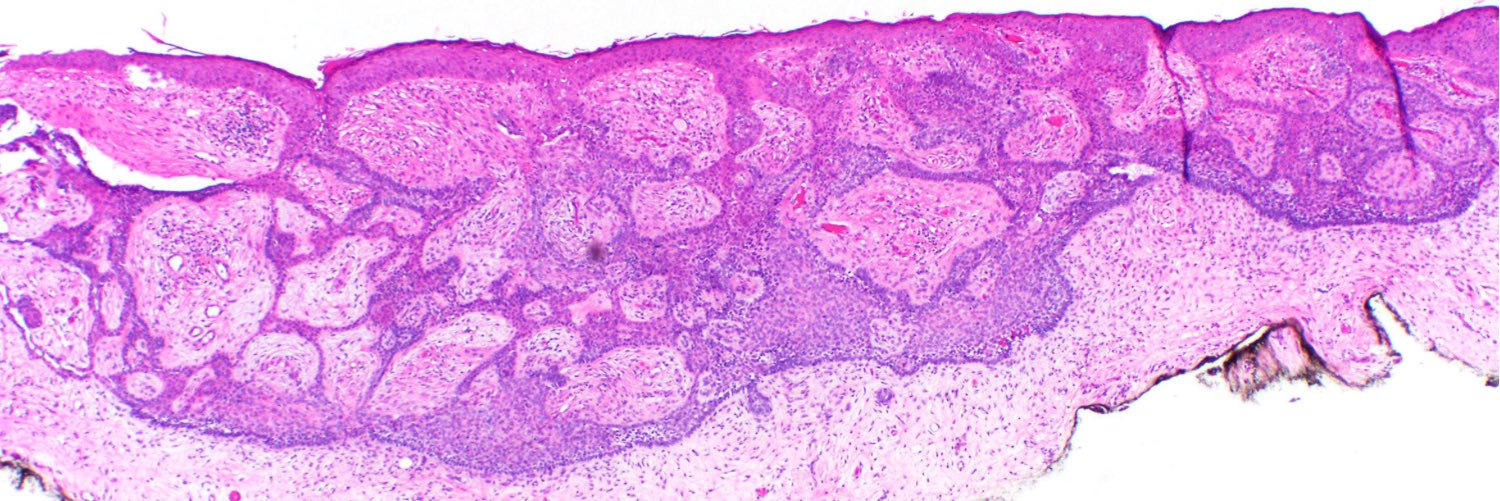

#ISDP #OlympicGames Spot diagnosis Case 18 - @JCandidoXavier SYRINGOCYSTADENOMA PAPILLIFERUM •It can occur in naevus sebaceus of Jadassohn •Endophytic crateriform lesion •Two layers of cells forming papillary and cystic structures • Numerous plasma cells #path #derm

Int Soc Dermpath tweet mediaInt Soc Dermpath tweet mediaInt Soc Dermpath tweet media